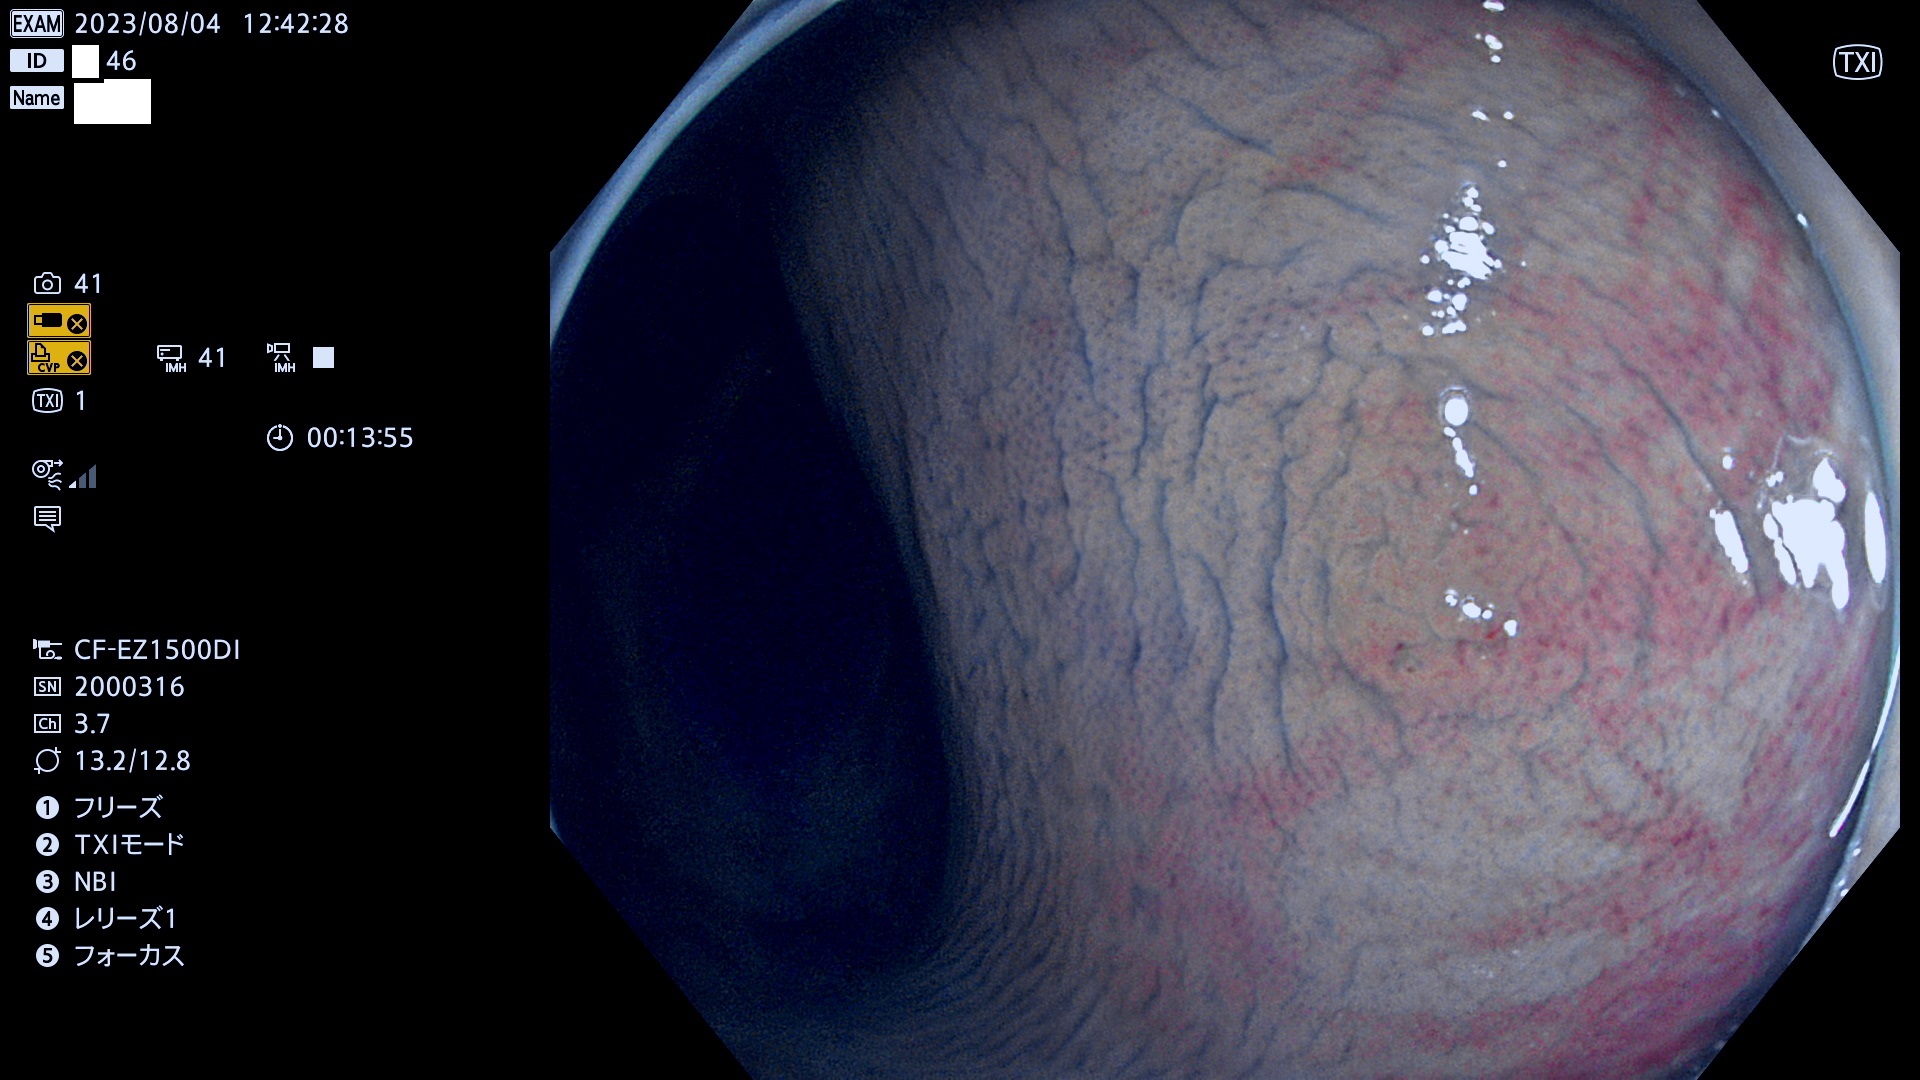

表面型腺腫(Flat Adenoma)の中で、完全に平坦な物をUb、陥凹している物をUcと呼びます。平坦隆起型(Ua)よりも、発見が難しく危険な病変です。このタイプは「内視鏡後・大腸癌の重要犯人」であり、この発見率は「腺腫発見率」よりも、重要な意味があります。

毎週の検査(木・金・土・日)に発見されたUb、Uc型・腺腫を、その週の日曜の夜にUPし1週間、提示します。

抽出の対象期間 2023年8月3日(木)〜8月6(日)の4日間(48件の検査)5件